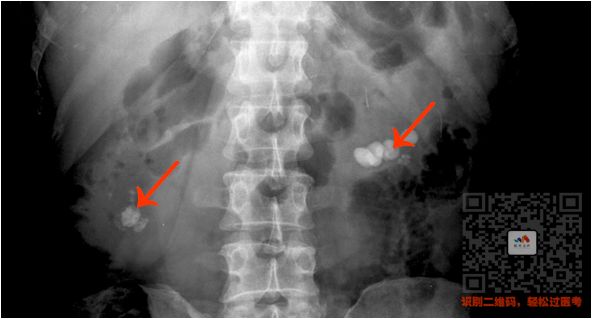

③ 泌尿系统阳性结石

病史:两侧腹部绞痛

特点:

肾和输尿管里面单个或成串的高密度影

看到两侧腹部有白色的圆点

就选肾结石/输尿管结石

看到下腹部的,就选膀胱结石

看图

(双肾结石)

(输尿管结石)